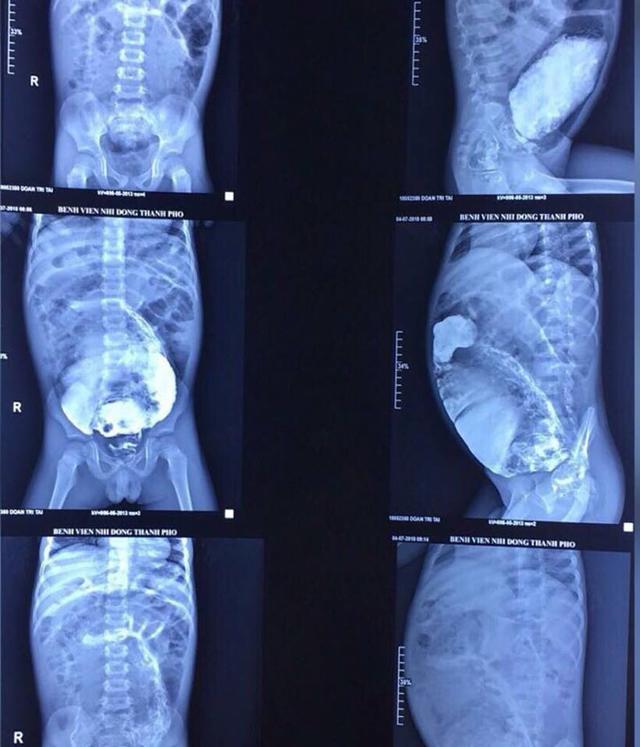

<p>Theo lời kể của chị H. (ngụ tại Rạch Giá, Kiên Giang) từ lúc mới sinh bé Đ.T (5 tuổi) luôn bị táo bón, bụng trướng to. Nhưng bé chỉ được chẩn đoán đại tràng dài và cho xuất viện. </p>    <p>Về nhà, bé tiếp tục đi ngoài khó. Độ 2-3 ngày, gia đình phải bơm cho bé đi ngoài nếu không bụng lại trướng lên. <em>“Vợ chồng tôi phải dùng thuốc bơm vào hậu môn cho con nhưng nó chỉ làm giảm nhẹ các triệu chứng chứ không thể trị dứt bệnh. Tôi đã tìm đến bác sĩ ở bệnh viện địa phương và trên Sài Gòn để chẩn đoán điều trị. </em></p>    <p><em>Các bác sĩ đã theo dõi bệnh tình của con suốt nhiều năm, nhưng vì hoàn cảnh khó khăn, ăn ở và đi lại bất tiện cộng thêm việc táo bón của con đáp ứng với thuốc nhuận tràng và thuốc bơm hậu môn, vì vậy gia đình đành cùng con chống chọi với căn bệnh suốt 5 năm”</em>, chị H. nói. </p>    <p align="center"><img  class="news-image"  alt="be trai bung phinh to nhu bau vi bi tao bon 5 nam, nhin phim chup con giat minh hon - 1" onclick="return openNewImage(this, '')" src='data:image/png;base64,iVBORw0KGgoAAAANSUhEUgAAAAEAAAABAQMAAAAl21bKAAAAA1BMVEX6+vqsEtnpAAAACklEQVQI12NgAAAAAgAB4iG8MwAAAABJRU5ErkJggg==' data-original="https://image.eva.vn/upload/3-2018/images/2018-07-18/be-trai-song-chung-voi-tao-bon-suot-5-nam-bung-phinh-to-vi-can-benh-de-gap-luc-sinh-2-1531883914-449-width640height747.jpg" /></p>    <p style="color:#0000ff;font-style:italic;text-align:center;">Đoạn phim chụp phần bụng phình ra.</p>    <p>Do lượng phân lớn tích trữ trong đoạn ruột giãn làm bụng bé T. phình to bất thường, các cơn đau ngày càng quằn quại nên gia đình phải đưa bé đến Bệnh Viện Nhi Đồng Thành Phố (TP.HCM) cấp cứu. </p>    <p>Tại đây, qua thăm khám và chụp phim, bác sĩ chẩn đoán bé bị hội chứng phình đại tràng bẩm sinh (Hirschsprung) khiến một đoạn đại tràng không có dây thần kinh để kiểm soát sự co bóp đại tràng.</p>    <p>Các bác sĩ tại bệnh viện đã tiến hành ca phẫu thuật kéo dài 3 giờ để cắt bỏ phần trực tràng bị phình dài gần 20 cm, dãn to 20 cm, cùng gần 3 kg phân ứ đọng bên trong dù đã được thụt tháo bơm rửa chuẩn bị trước phẫu thuật.</p>    <p align="center"><img  class="news-image"  alt="be trai bung phinh to nhu bau vi bi tao bon 5 nam, nhin phim chup con giat minh hon - 2" onclick="return openNewImage(this, '')" src='data:image/png;base64,iVBORw0KGgoAAAANSUhEUgAAAAEAAAABAQMAAAAl21bKAAAAA1BMVEX6+vqsEtnpAAAACklEQVQI12NgAAAAAgAB4iG8MwAAAABJRU5ErkJggg==' data-original="https://image.eva.vn/upload/3-2018/images/2018-07-18/be-trai-song-chung-voi-tao-bon-suot-5-nam-bung-phinh-to-vi-can-benh-de-gap-luc-sinh-1-1531883913-318-width640height435.jpg" /></p>    <p style="color:#0000ff;font-style:italic;text-align:center;">Các bác sĩ tiến hành phẫu thuật cho bệnh nhi.</p>    <p>Sau hơn 15 ngày nằm điều trị tại khoa Ngoại Tổng Hợp, bệnh nhi ăn uống và tự đi tiêu thoải mái, bụng xẹp hẳn. Hiện bé đã được xuất viện về nhà. </p>    <p>BS Nguyễn Thị Cẩm Xuyên - khoa Ngoại Tổng hợp cho biết bệnh phình đại tràng bẩm sinh do nguyên nhân vô hạch chiếm vị trí hàng đầu trong hội chứng tắc ruột ở trẻ sơ sinh. <em>“Mới chào đời, trẻ mắc bệnh phình đại tràng bẩm sinh do vô hạch sẽ không đi tiêu phân su trong ngày đầu tiên, trong khi trẻ bình thường sẽ đi được. Những ngày sau đó, bé vẫn tiếp tục táo bón và người nhà phải dùng thuốc bơm vào hậu môn cho bé”,</em> bác sĩ Xuyên nói. </p>    <p>Khi ấy, một số bé sẽ đi ngoài được, còn một số bé vẫn không thể. Những bé không đi ngoài được, người nhà sẽ đưa bé đến bệnh viện, sau đó bệnh viện phải đặt ống thông vào hậu môn, bơm nước muối sinh lý (thụt tháo) để giúp bé đi ngoài.</p>    <p align="center"><img  class="news-image"  alt="be trai bung phinh to nhu bau vi bi tao bon 5 nam, nhin phim chup con giat minh hon - 3" onclick="return openNewImage(this, '')" src='data:image/png;base64,iVBORw0KGgoAAAANSUhEUgAAAAEAAAABAQMAAAAl21bKAAAAA1BMVEX6+vqsEtnpAAAACklEQVQI12NgAAAAAgAB4iG8MwAAAABJRU5ErkJggg==' data-original="https://image.eva.vn/upload/3-2018/images/2018-07-18/be-trai-song-chung-voi-tao-bon-suot-5-nam-bung-phinh-to-vi-can-benh-de-gap-luc-sinh-3-1531883914-875-width640height808.jpg" /></p>    <p style="color:#0000ff;font-style:italic;text-align:center;">Hiện tại sức khỏe bé trai đã ổn định và được xuất viện.</p>    <p>Bác sĩ Xuyên cho biết thêm không phải trẻ nào mắc bệnh này cũng có thể phát hiện trong giai đoạn sơ sinh. Do vậy khi xuất viện, bác sĩ hẹn tái khám thì người nhà bệnh nhi nên tuân thủ. Bác sĩ Xuyên cung cấp thêm:  </p>    <p>- Tình trạng bệnh nặng hay nhẹ, phát hiện sớm hay trễ tùy thuộc nhiều vào đoạn ruột vô hạch (không có hạch thần kinh trong thành ruột) dài hay ngắn.</p>    <p>- Trẻ có đoạn ruột vô hạch ngắn, bụng sẽ trướng lên, không đi cầu được nhưng chỉ cần mua ống thuốc bơm vào hậu môn sẽ giúp trẻ đi tiêu. Vì vậy, nhiều gia đình thường chấp nhận giải pháp này và không đưa trẻ đến bệnh viện khám lại. Tình trạng táo bón sẽ kéo dài trong nhiều năm.</p>    <p>- Trẻ có đoạn ruột vô hạch dài thì dù có bơm thuốc vẫn không giúp trẻ đi tiêu bình thường nên thường phải đưa trẻ đến bệnh viện thụt tháo. Lâu ngày đoạn ruột vô hạch này không hoạt động sẽ bị teo nhỏ và đại tràng nằm ở phía trên bị phình dãn ra, ứ đọng ngày càng nhiều phân và chứng táo bón sẽ kháng trị với các loại thuốc nhuận tràng.</p>    <p>Khi phát hiện trẻ bị bệnh cần cho đi mổ sớm bởi mổ càng sớm, ruột của trẻ sơ sinh ít viêm dính, đặc biệt chức năng đi tiêu sau mổ được hoàn thiện tốt hơn. Phẫu thuật muộn, khi trẻ càng lớn, tình trạng ứ đọng phân càng kéo dài, dẫn đến trẻ chậm phát triển thể chất, nguy cơ bị viêm ruột trước và sau mổ càng cao, có thể dẫn đến nhiễm trùng huyết, nhiễm độc thậm chí tử vong.</p><div class="evtBox evtBoxPrBt">  <div class="evtBoxImg"><img alt="Mẹ dùng lá cây nấu cháo chữa táo bón, con 1 tuổi đi tiểu ra máu, nhập viện cấp cứu" class="img_bai_lien_quan_tren" src="http://image.eva.vn/upload/2-2018/images/2018-05-31/1527739884-818-thumbnail.jpg" /></div>    <div class="evtBoxRt">  <div class="sap clrTit mrT10 mrB10">Mẹ dùng lá cây nấu cháo chữa táo bón, con 1 tuổi đi tiểu ra máu, nhập viện cấp cứu</div>    <div class="sap"><span class="clrTit">Sau 2 ngày ăn cháo lá cây để chữa táo bón, bé gái 1 tuổi phải nhập viện cấp cứu vì đi tiểu ra máu, da xanh nhợt nhạt.</span></div>    <div class="btnSe">Bấm xem >></div>  </div>  </div><div class="athr txtrt pdB10 clrF"><span class="bld">Theo Khai Tâm (Khám phá)</span></div>